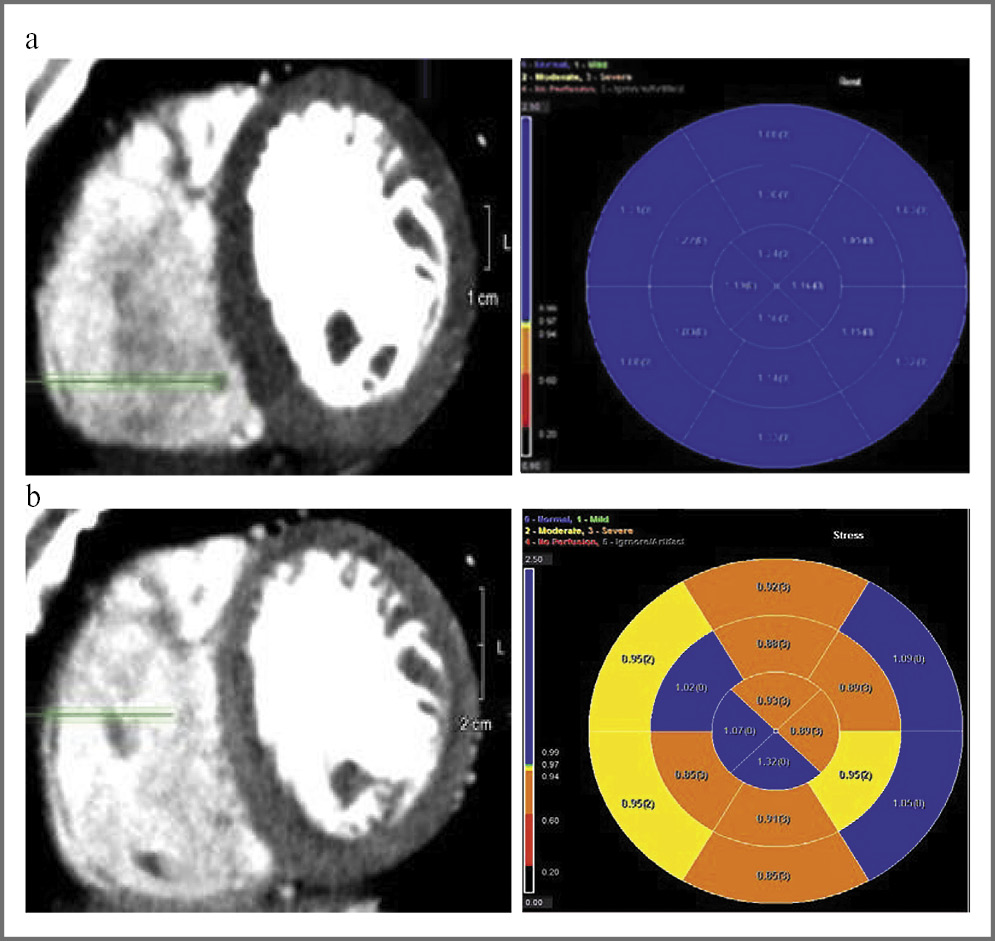

Рис. 1

a – ОбКТ сердца с фармакологической пробой с АТФ, фаза покоя. Изображение миокарда ЛЖ в артериальную фазу контрастирования, поперечный срез на уровне средних сегментов, и детализированная полярная карта распределения КТП. Субэндокардиальные дефекты перфузии миокарда ЛЖ не определяются. Значение КТП во всех сегментах миокарда ЛЖ более 0,99;

b – ОбКТ сердца с фармакологической пробой с АТФ, фаза нагрузки. Изображение миокарда ЛЖ в артериальную фазу контрастирования, поперечный срез на том же уровне, что и в фазу покоя, и детализированная полярная карта распределения КТП. Определяются субэндокардиальные дефекты контрастирования всех сегментов передней, перегородочной, нижней стенок, средних сегментов боковой стенки миокарда ЛЖ. Значение КТП в перечисленных сегментах миокарда ЛЖ ниже 0,99.

Fig 1:

a – cardiac volumetric computed tomography (VCT) of the heart with adenosine triphosphate (ATP) pharmacological test, resting phase. Image of the left ventricle (LV) myocardium in the arterial phase of contrast-enhancing, cross-section at the level of the middle segments, and a detailed polar map of the transmural perfusion coefficient distribution. Subendocardial defects of LV myocardial perfusion were not detected. The transmural perfusion coefficient value in all segments of the LV myocardium was more than 0.99;

b – cardiac VCT with pharmacological sample from ATP, loading phase. Image of the LV myocardium in the arterial phase of contrast-enhancing, cross-section at the same level as in the resting phase, and a detailed polar map of the transmural perfusion coefficient distribution. Subendocardial contrast-uptake defects in all segments of the anterior, sepal, and lower walls and middle segments of the lateral wall of the LV myocardium were observed. The transmural perfusion coefficient value in the above segments of the LV myocardium was below 0.99.

На рис. 1 приведен пример качественного (визуального) и полуколичественного (по показателю КТП) выявления дефектов перфузии миокарда ЛЖ в ответ на введение АТФ при ОбКТ сердца.